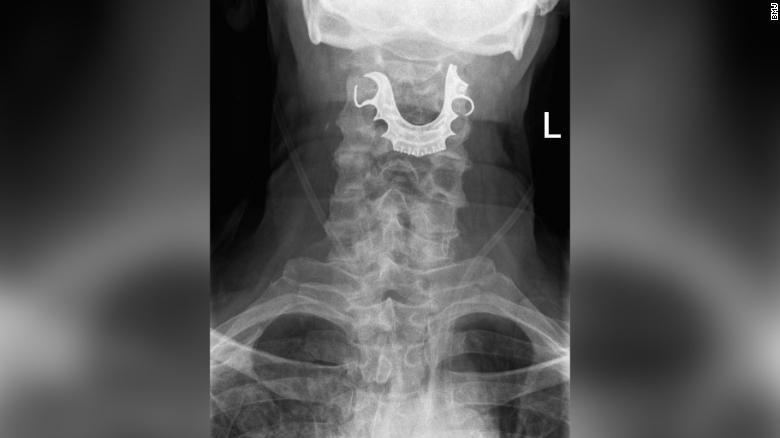

Eventually a diagnostic procedure identified a semicircular object lying across his vocal cords, which had caused internal blistering and swelling.

最終,一個(gè)診斷程序發(fā)現(xiàn)他的聲帶上橫著一個(gè)半圓形物體,導(dǎo)致了聲帶內(nèi)部起泡和腫脹。